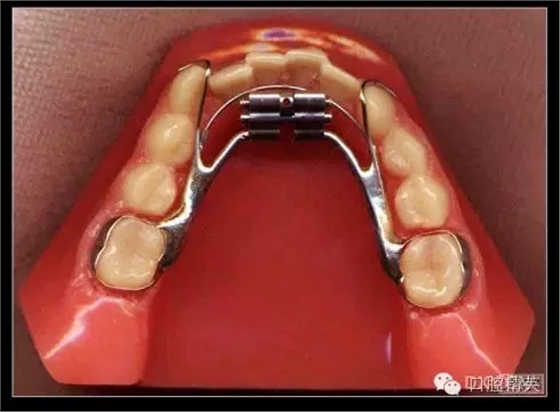

三、擴弓器

很多牙列不齊常伴隨牙弓過窄,所以擴弓器是正畸醫(yī)生的好伙伴,它可以以多種形態(tài)和您見面。